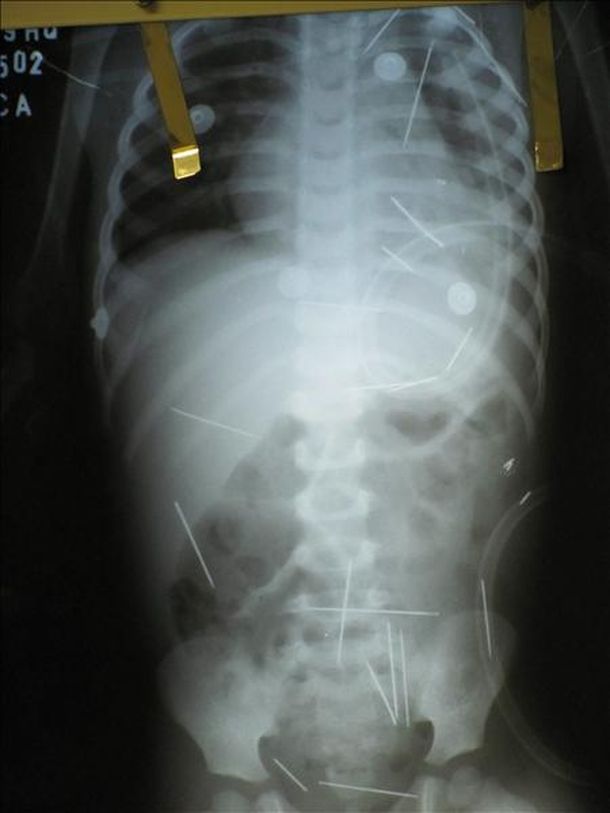

El domingo, el pequeño fue sometido a exámenes más detallados en otro hospital de la ciudad de Barreirinhas, donde las radiografías revelaron que tiene en total 50 objetos metálicos esparcidos por todo el cuerpo entre el abdomen, el cuello, el tórax y hasta las piernas.

Un último informe médico reveló, además, que una de las agujas le perforó un pulmón. El menor continúa internado en estado grave.

La Policía abrió una investigación del caso mientras que los médicos responsables consideran "difícil" la posibilidad de que el menor se tragase las agujas ya que éstas aparecen diseminadas por todo el cuerpo.